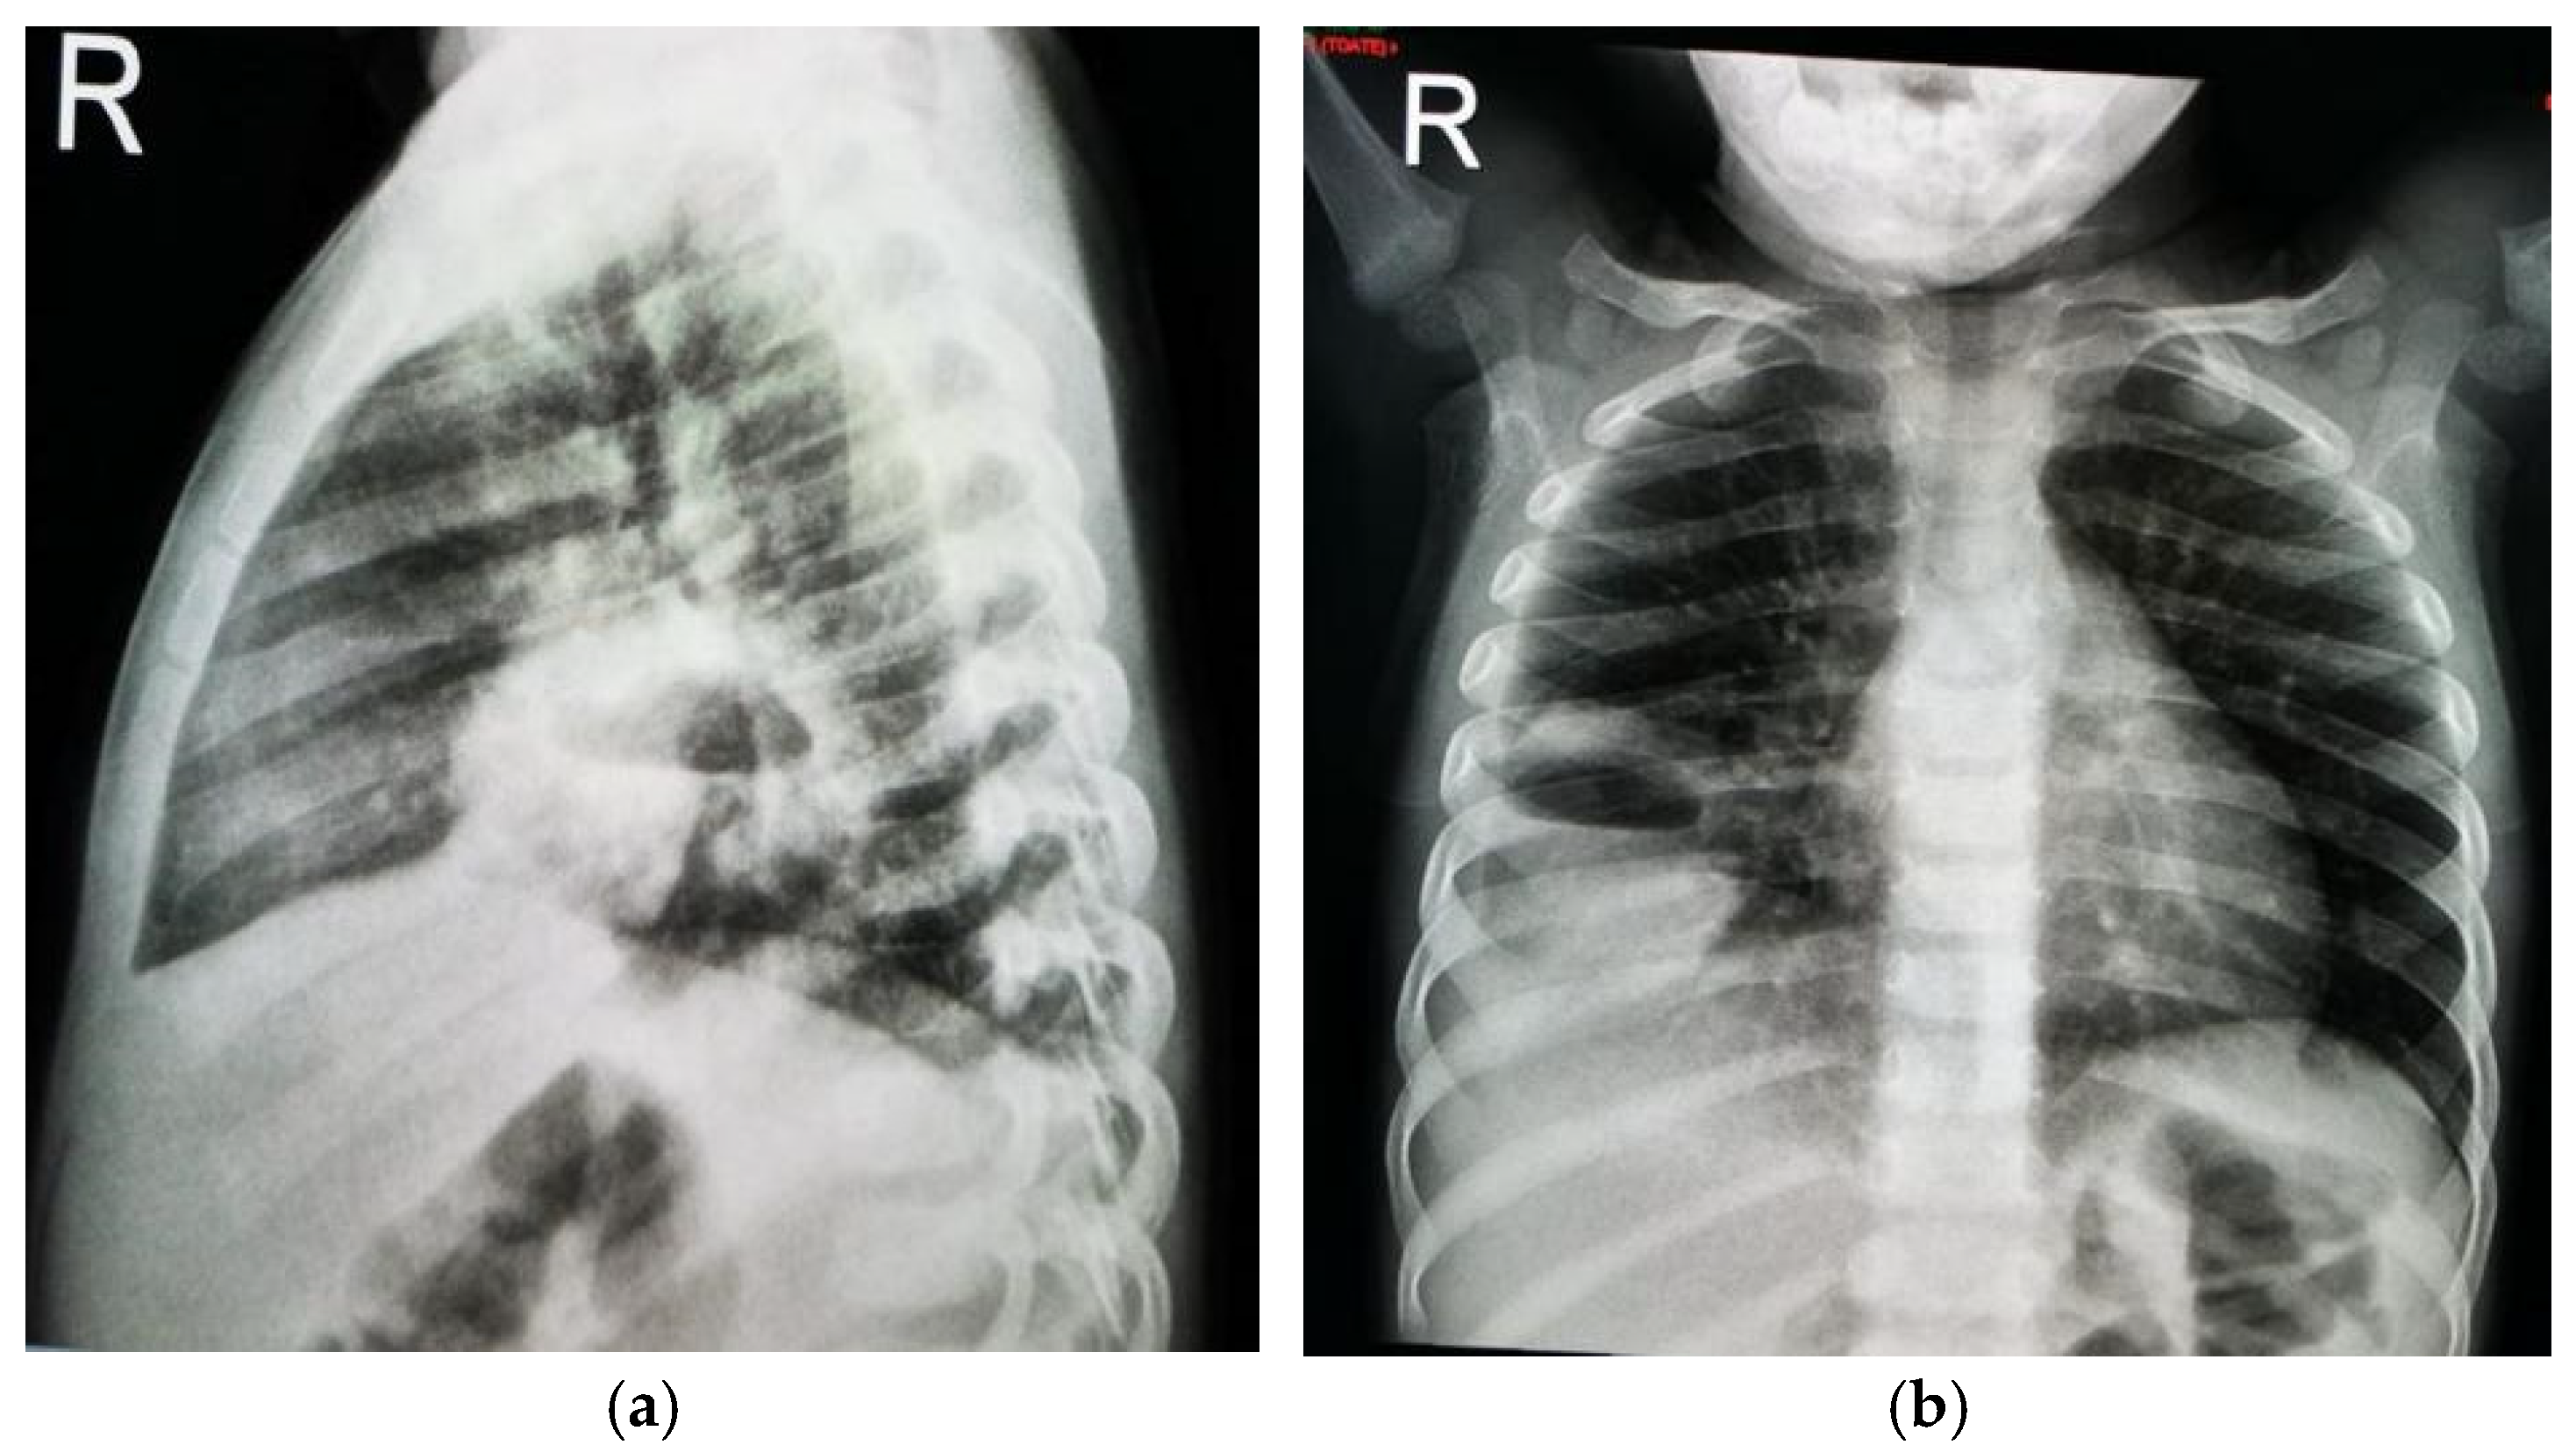

1.9.1. Case 1

1.9.2. Case 2